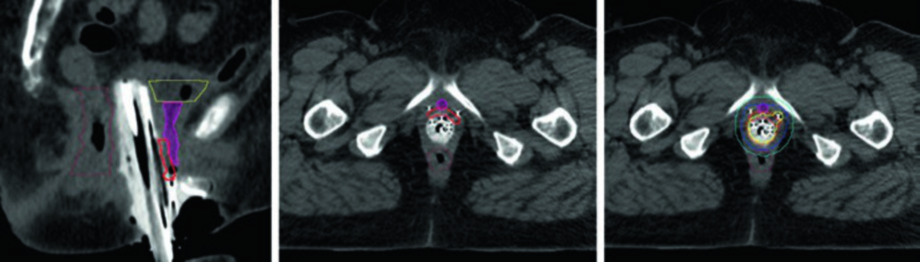

Câncer de Vulva e Considerações Finais

No câncer de vulva, a quimiorradioterapia concomitante é a abordagem preferida para estádios II-IVA. A braquiterapia como reforço deve ser considerada em pacientes com extensão vaginal ou que toleram mal a fase inicial de EBRT. Para estádio I, a braquiterapia não faz parte do tratamento padrão — exceto em pacientes clinicamente inoperáveis.